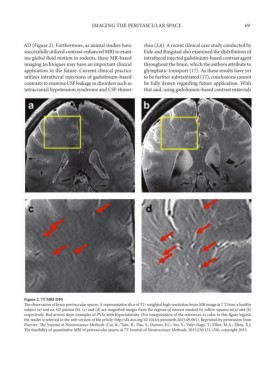

Figure 2. 7T MRI DPS

The observation of brain perivascular spaces. A representative slice of T2- weighted high resolution brain MR image at 7 T from a healthy

subject (a) and an AD patient (b). (c) and (d) are magnified images from the regions of interest marked by yellow squares in(a) and (b)

respectively. Red arrows show examples of PVSs with hyperintensity. (For interpretation of the references to color in this figure legend,

the reader is referred to the web version of the article: http://dx.doi.org/10.1016/j.jneumeth.2015.09.001). Reprinted by permission from

Elsevier: The Journal of Neuroscience Methods (Cai, K.; Tain, R.; Das, S.; Damen, F.C.; Sui, Y.; Valyi-Nagy, T.; Elliot, M.A.; Zhou, X.J.

The feasibility of quantitative MRI of perivascular spaces at 7T. Journal of Neuroscience Methods. 2015;256:151-156), copyright 2015.